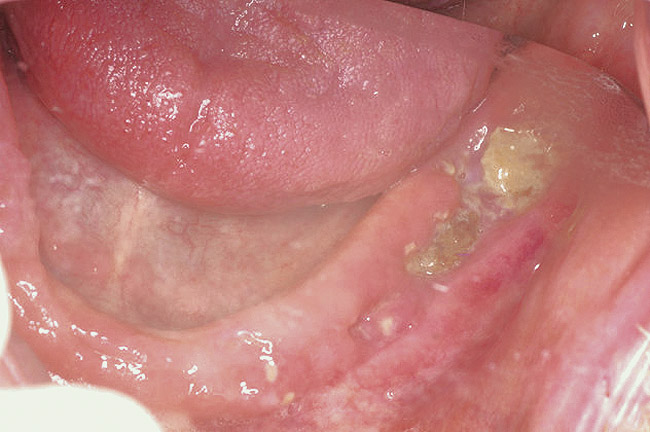

Bisphosphonate-related osteonecrosis of the jaws (BRONJ) is characterized by the presence of exposed bone in the oral cavity for more than 8 weeks in a patient who has been taking bisphosphonates and who has not had any radiation therapy in the oral cavity3 (Figure 1). The risk of BRONJ from the use of oral bisphosphonates is very low, currently about 1%.8 Most researchers believe this incidence is so low because it takes many years for the drug to saturate the bone. Most cases of BRONJ from oral bisphosphonates occur after at least 3 years of drug use.9 However, a recent study by Cartsos et al of over 700,000 medical claims found no increased incidence of inflammatory conditions, including osteonecrosis.10

Figure 1  Exposed bone in the mandibular jaw that is characteristic of BRONJ. Photo courtesy of Robert Marx, DDS.

Figure 1